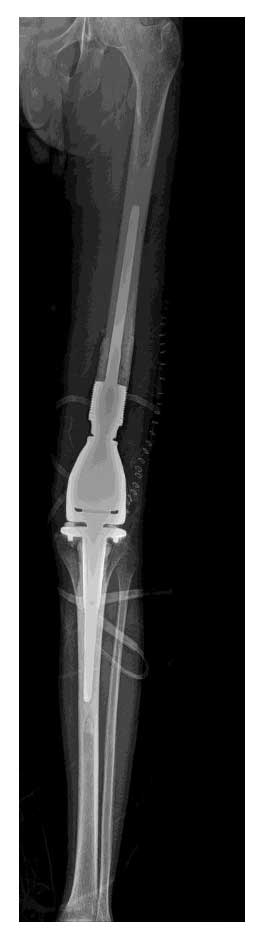

Hastaya kemoterapi tedavisinin ardından geniş (ekstraartiküler) rezeksiyon uygulandı. Tümörlü kemik çıkarılarak eksize edilen bölge distal femur tümör protezi ile yeniden yapılandırıldı. Bu yöntem sayesinde hastanın diz eklemi stabilitesi ve fonksiyonu korunmuş oldu.

Ameliyat sonrası süreç sorunsuz ilerlemiş, hastanın yürüme fonksiyonu korunmuştur. Hasta yara iyileşmesini takiben onkolojik takip ve rehabilitasyon sürecine yönlendirilmiştir.

Ameliyat Sonrası: Röntgende rezeksiyon sonrası uygulanan tümör protezi görülmekte.